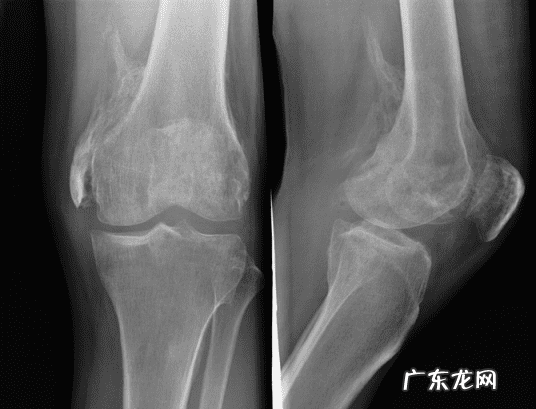

进行性骨化性肌炎

(2)进行性骨化性肌炎为先天性遗传性疾病患 , 有时表现为家族性疾患 。男性较多见 , 常发病于婴儿或小儿 。常于生后几岁就被发现患此疾病 。早期症状为受累部疼痛、热、肿胀 , 而后 , 常于背、颈、肩部皮下组织内出现硬块 , 剧烈疼痛或压痛 。此时 , 可能合并发烧 。随着病灶的胶样化 , 皮下组织的肿块逐渐缩小 , 以至变硬而固定的肿块 。至此 , 急性期症状暂告消失 , x线检查已可知病灶中有钙盐沉着 。接着又可有新的病灶出现 。因此 , 可出现一组一组的肌肉、肌腱、韧带相继受累现象 。轻微的外伤就可促使病情加重 , 因此应避免做活体组织检查 。大约于30岁以后 , 此病就停止进展 。本病预后不佳 , 多见于呼吸障碍或嚼饥骨化所致的慢性饥饿 。运用中医中药、辨证施治 , 采用行气活血 , 化瘀通络 , 消肿散结的方法治疗本病 , 通过整体调节使机体阴阳气血达到平衡有序的目的 。本病治疗越早效果越佳 。中药外敷与口服中药冲剂相结合 , 治疗该疾病疗效高、恢复快 , 可使钙化的肌肉吸收 , 功能恢复 , 达到康复的目的 。